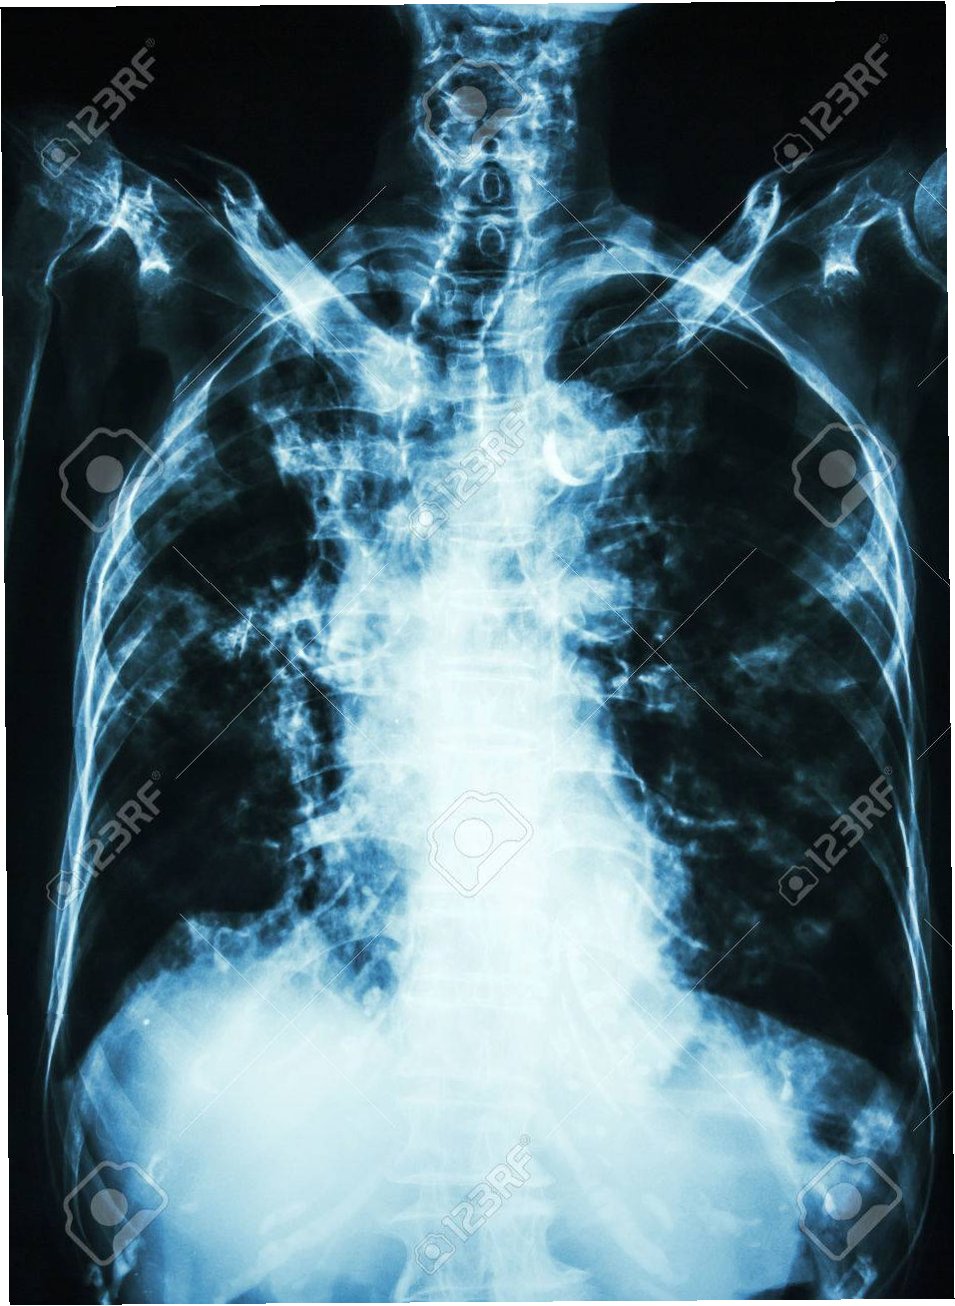

사고 발생 5년 뒤인 2019년부터 밤마다 원인 불명의 고열에 시달리던 사이먼스 씨는 병원을 찾았습니다. CT 검사 결과, 사고 당시 흡입했던 먼지 파편이 폐 깊숙이 들어가 배출되지 못하고 딱딱하게 굳어 왼쪽 폐 기관지를 완전히 막고 있다는 충격적인 사실이 밝혀졌습니다. 그는 '기계에 깔려 움직일 수 없을 때 먼지를 들이마셨는데, 그게 깊이 들어가 굳어버렸다'고 당시를 설명했습니다.

의료진은 이물질이 기관지에 박히면서 신체가 칼슘으로 둘러싸 격리하는 과정에서 석회화가 진행된 것으로 판단했습니다. 정밀 검사 결과, 좌측 폐는 5년간의 감염으로 기능을 완전히 상실한 상태였습니다. 의료진은 처음에는 석회화된 부분만 제거하려 했으나, 손상 범위가 너무 넓어 결국 폐 전체를 적출해야 한다는 결론에 이르렀습니다. 사이먼스 씨는 결국 왼쪽 폐를 떼어내는 수술을 받았습니다.